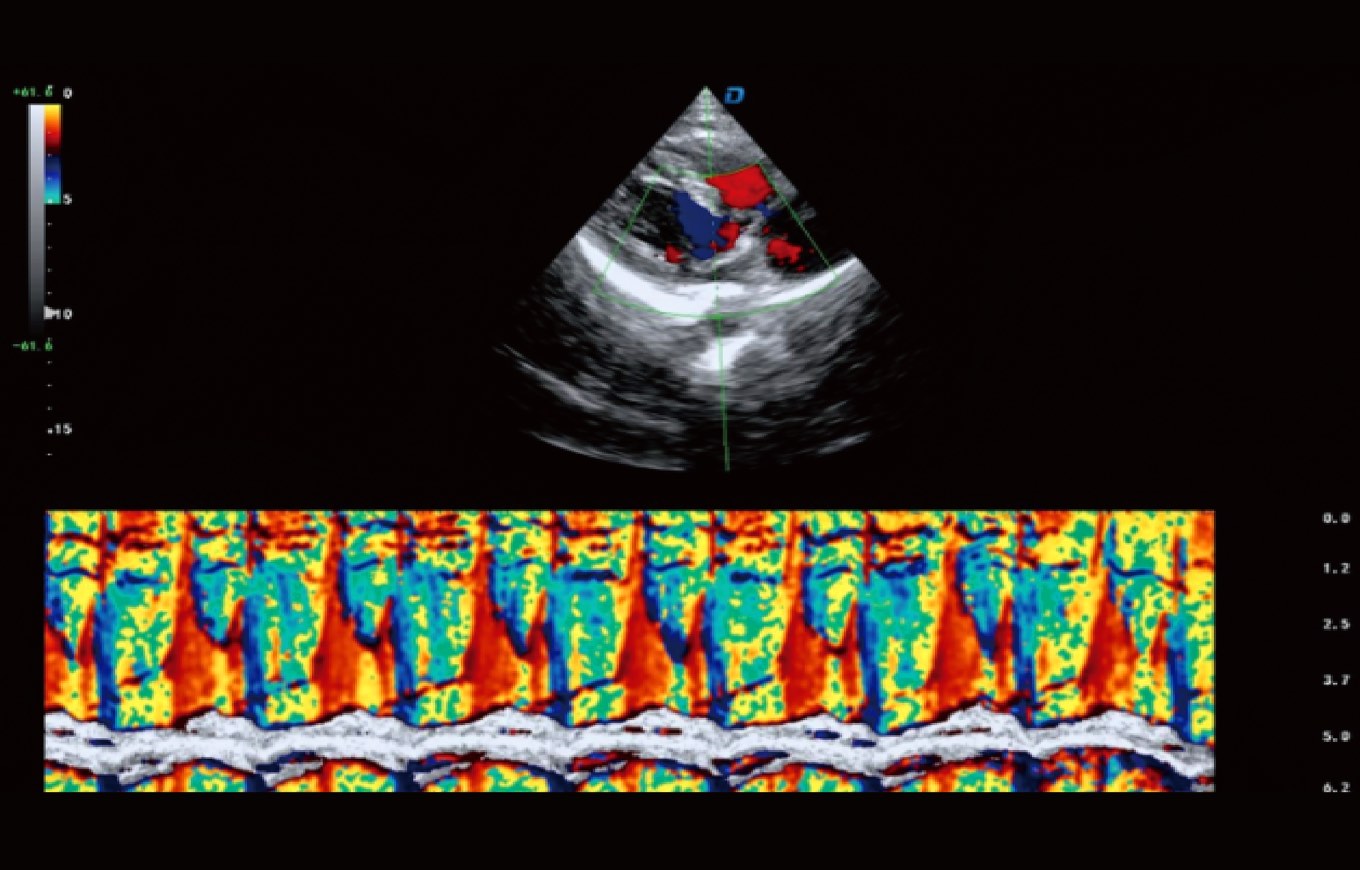

Pulsed -wave Doppler (PWD) dan Continuous-wave Doppler (CWD), dll. adalah fungsi pencitraan dasar dari

, yang mengevaluasi fungsi berbagai bagian sistem jantung tubuh.